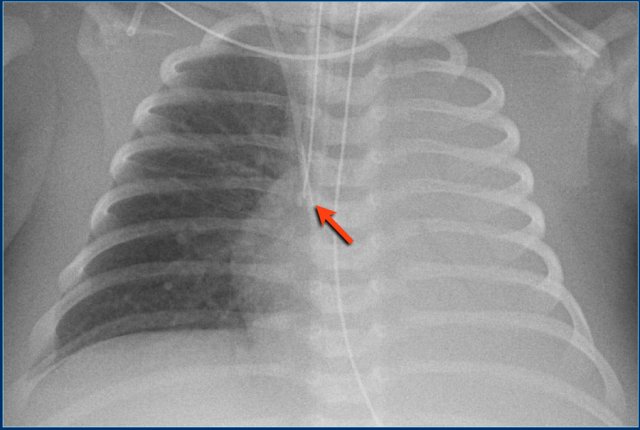

Here a good positioned tube in a patient with a pneumothorax on the left.

Endotracheal tube (2)

Study the image.

Then continue reading.

The findings are:

• Right mainstem bronchus intubation with atelectasis of the entire left lung.